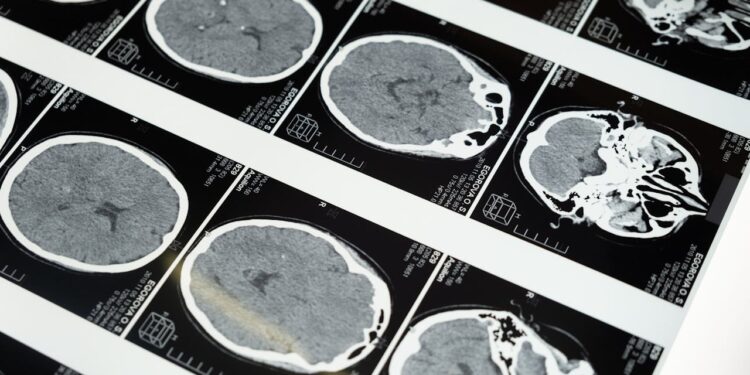

Duecento quesiti clinici sono stati proposti a diversi modelli di intelligenza artificiale, spaziando dalle patologie ematologiche alle neoplasie più complesse. Il verdetto è stato secco: il 70% delle risposte conteneva almeno un errore clinico, mentre il 30% presentava riferimenti bibliografici inventati, privi di qualsiasi riscontro scientifico. E non si trattava di sfumature: in più casi l’algoritmo ha confuso carcinomi distinti o descritto tumori mai diagnosticati. La lucidità dell’esposizione ha reso più insidioso l’errore, mascherandolo sotto una coltre di apparente autorevolezza.

Un team di ricercatori ha progettato cinque scenari simulati, modellati su reali casi diagnostici. Ogni quadro clinico è stato costruito seguendo le linee guida più recenti e approvato da specialisti esperti. Lo scopo era sondare il margine d’affidabilità di un chatbot messo nelle condizioni di operare come assistente decisionale. Solo il 32% delle risposte si è rivelato privo di errori significativi. Il resto del campione ha esibito diagnosi scorrette, interpretazioni fuorvianti e un uso disinvolto di fonti inattendibili.

Un secondo studio, condotto in una struttura ospedaliera milanese, ha esteso la sperimentazione all’ambito neurologico. ChatGPT e Gemini sono stati messi alla prova durante prime visite neurologiche su 28 pazienti veri. I medici in carne ed ossa hanno centrato la diagnosi nel 75% dei casi. L’intelligenza artificiale, invece, si è fermata al 54% e al 46% rispettivamente. Oltre alle incertezze diagnostiche, i due modelli tendevano a raccomandare un numero spropositato di esami, con una media che oscillava tra il 17% e il 25%, alimentando un rischio di iper-medicalizzazione.